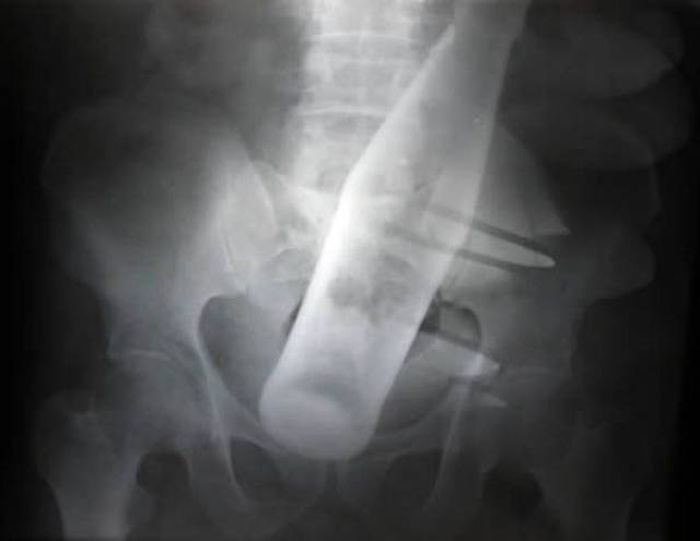

Предметы, которые не очень хочется видеть внутри себя

Под рентгеновскими лучами порой видны не только внутренние органы и кости, но и инородные тела, попавшие в организм

Истории попадания этих предметов в организм могут быть самыми невероятными и запутанными, но больше всего медиков интересует процесс их извлечения, впрочем, в этом заинтересованы и сами пациенты, допустившие нечто подобное со своим телом.